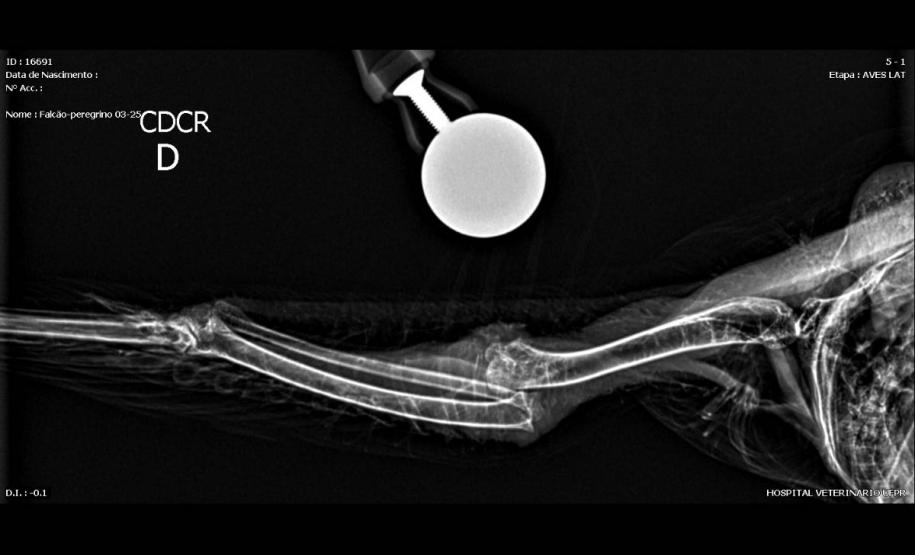

O animal foi encaminhado na semana passada para a clínica veterinária da Universidade Federal do Paraná (UFPR) em Palotina, onde permanece sob tratamento antes da avaliação que vai definir se poderá retornar à natureza. A anilha encontrada na ave também revelou que o falcão é originário de Ocean City, cidade do Estado de Maryland, nos Estados Unidos, e viajou 7.300 quilômetros até chegar ao Paraná.